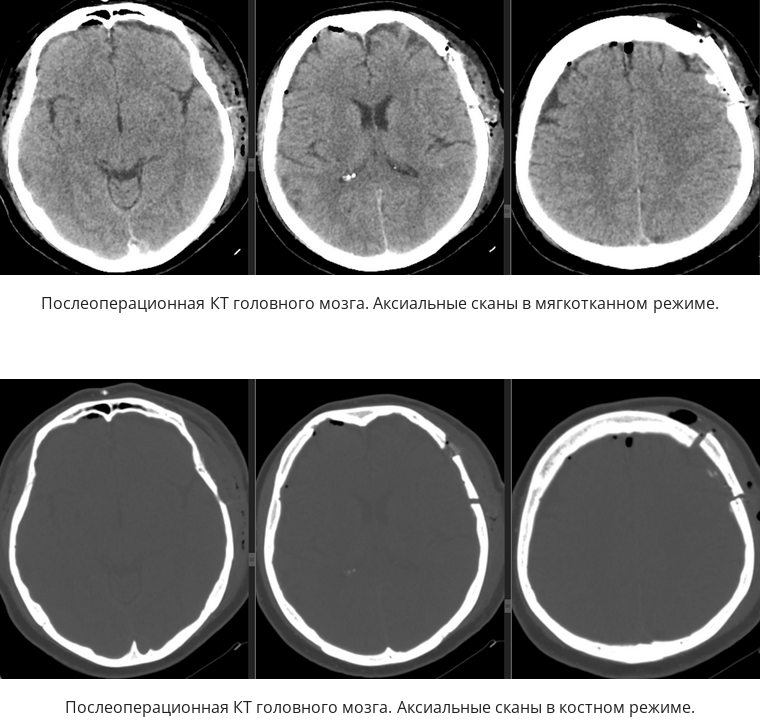

Инсульт удаление гематомы